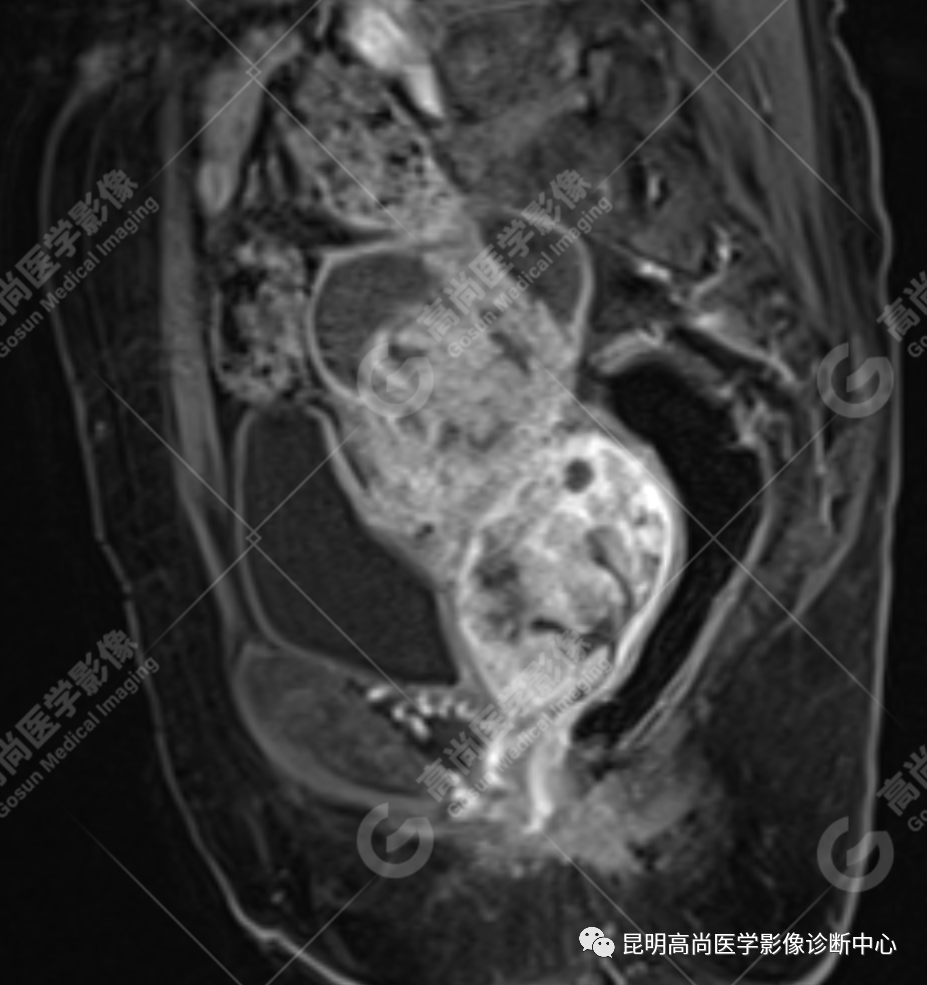

影像诊断

子宫、附件未见显示;下腹部及盆腔内巨大占位,考虑恶性肿瘤,肉瘤可能,阴道及肛管受侵,建议活检。

不规则菜花状或息肉状肿物,子宫内膜正常 T2WI 清晰连续的高信号消失,取而代之是中高、高信号,不均匀混杂信号,信号强度低于内膜正常信号强度,T1WI 上内膜信号增高,子宫肌层明显变薄,未受侵者肌层信号均匀,因肿物组织来源不同,病变信号复杂,以 T2WI 表现为等高混杂信号为主。因病灶较大,可合并囊变坏死及肿瘤出血。

肌层到肿块内的血管流空信号,可提示肿瘤内有血供丰富的肉瘤成分,血管流空信号在子宫内膜癌中未见报道,但在子宫平滑肌瘤、平滑肌肉瘤中可见。